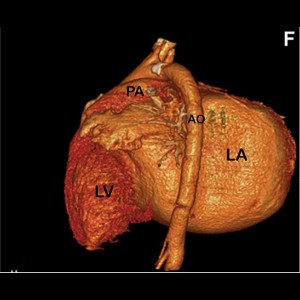

Giant Left Atrium Due to Rheumatic Mitral Regurgitation

Giant Left Atrium Due to Rheumatic Mitral Regurgitation

Giant Left Atrium Due to Rheumatic Mitral Regurgitation

Giant Left Atrium Due to Rheumatic Mitral Regurgitation